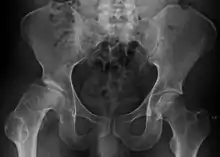

Radiograph of a person with Legg–Calvé–Perthes disease

Legg–Calvé–Perthes disease (LCPD) is a childhood hip disorder initiated by a disruption of blood flow to the head of the femur. Due to the lack of blood flow, the bone dies (osteonecrosis or avascular necrosis) and stops growing. Over time, healing occurs by new blood vessels infiltrating the dead bone and removing the necrotic bone which leads to a loss of bone mass and a weakening of the femoral head.

The condition is most commonly found in children between the ages of 4 and 8, but it can occur in children between the ages of 2 and 15. It can produce a permanent deformity of the femoral head, which increases the risk of developing osteoarthritis in adults. Perthes is a form of osteochondritis which affects only the hip. Bilateral Perthes, which means both hips are affected, should always be investigated to rule out multiple epiphyseal dysplasia.